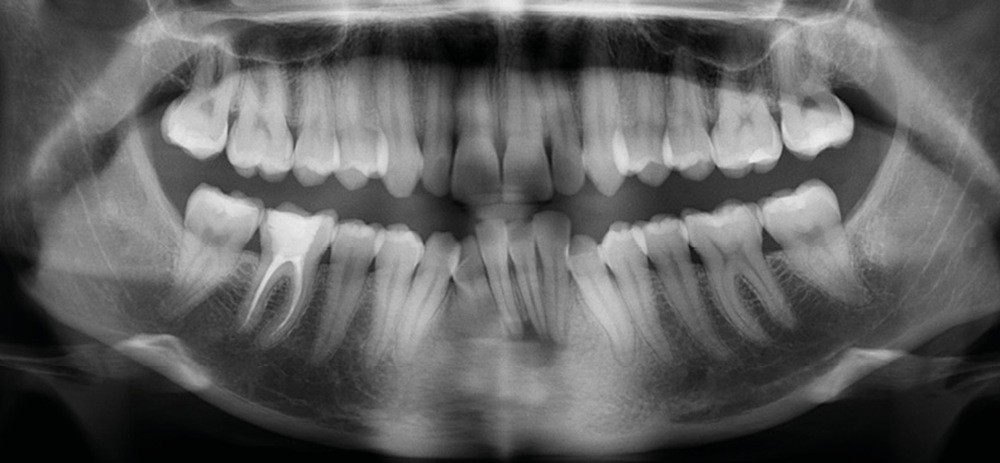

Examens complémentaires (fig. 3a,b)

À la radiographie panoramique, 31 présente une importante image apicale, confirmée par une radiographie rétroalvéolaire et également visible sur la téléradiographie de profil.

Cette dernière montre un schéma squelettique de Classe I et une typologie verticale normodivergente. Les rapports incisifs sont normaux et l’épaisseur des tissus mentonniers est insuffisante pour obtenir la fermeture buccale sans contraction. La symphyse est fine et l’incisive est centrée sur celle-ci.